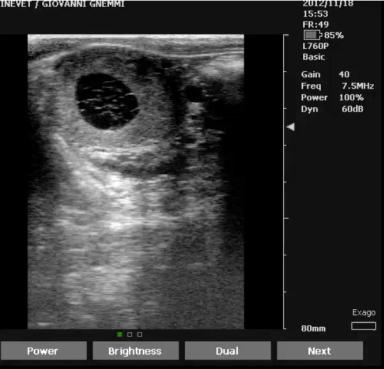

И снова о УЗИ семенников у разных видов животных.

Всем добрый день!

Помню, что обещал выкладывать больше материала по УЗИ молочных КРС, но материала у меня по этой теме не на столько много, так как работаю чуть ...

И также есть возможность работы по фертильности самцов, напишу тут чтобы в опроснике не спойлерить) это был снимок семенника у быка породы Ангус)